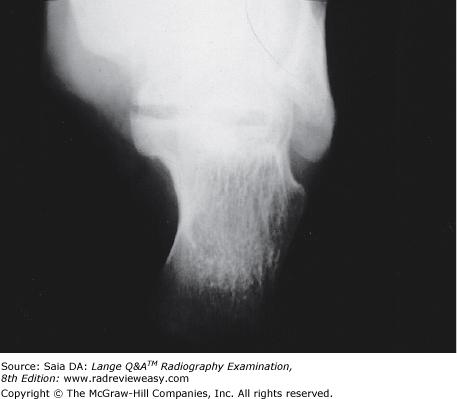

AP stress studies of the ankle may be performed

C 2 and 3 only

-After forceful eversion or inversion injuries of the ankle, AP stress studies are valuable to confirm the presence of a ligament tear. Keeping the ankle in an AP position, the physician guides the ankle into inversion and eversion maneuvers. Characteristic changes in the relationship of the talus, tibia, and fibula will indicate ligament injury. Inversion stress demonstrates the lateral ligament, whereas eversion stress demonstrates the medial ligament. A fractured ankle would not be manipulated in this manner.